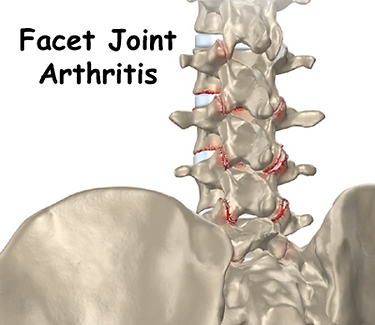

Can mobilize a facet joint that has arthritis and an adjacent facet cyst temporarily irritate a nerve root? What if the patient does not get good and/or sustained relief from a combination of epidural steroid injections and facet injections?